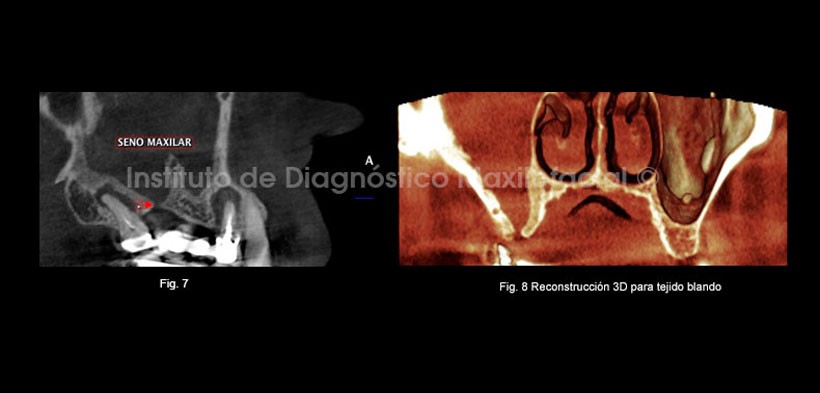

En los cortes axiales se observa el seno maxilar derecho ocupado y aumento de la densidad ósea circundante, caracterizada por el engrosamiento de las paredes del seno maxilar derecho imágenes compatibles con sinusitis maxilar crónica de origen odontogénica, además la presencia de una imagen hiperdensa en seno maxilar izquierdo compatible con Antrolito. (Fig. 5, 6, 7, 8).